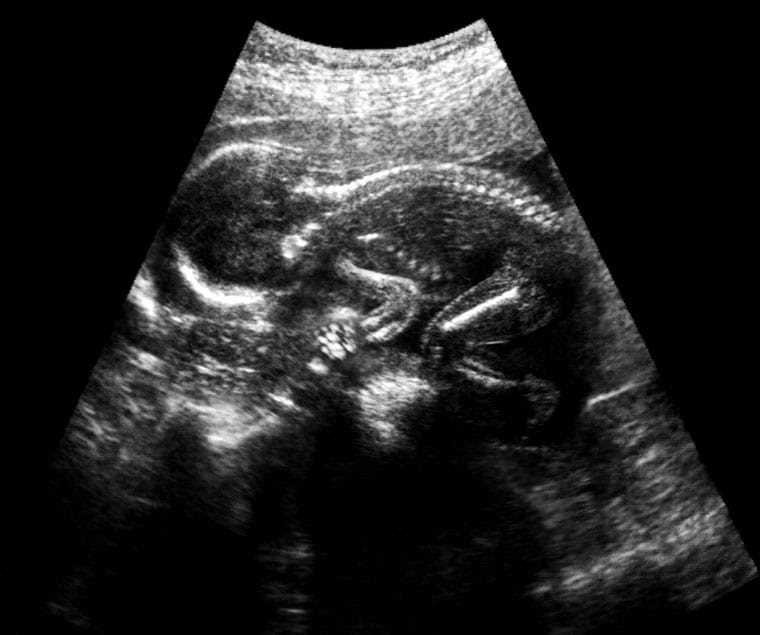

אמנם כניסה להיריון, חודשי ההיריון ולידה הם טבעיים וחלק בלתי נפרד מהמהות האנושית, הוא גם מלא בסכנות וסיכונים לאם ולעובר. פריצות הדרך הטכנולוגיות והתקדמות הרפואה הביאו לירידה משמעותית בלידת תינוקות עם מגבלות, גם בשל היכולת לאתר ולאבחן מומים בשלבים מוקדים של ההיריון ולאפשר להורים להחליט את ההחלטה, המורכבת והכואבת, האם להביא את ההיריון לסיומו או להמשיך אותו. מעקב היריון נועד למעשה להעלות את הסיכוי להיריון תקין, לידה תקינה ולידת ילד בריא תוך שמירה על שלום האישה ההרה. תפקיד הרופא המטפל הוא הרבה מעבר לביצוע המעקב הטכני, בין היתר עליו להקפיד לשלוח את המטופלת לבדיקות, להסביר לה את חשיבות הבדיקות, לעבור על התוצאות וכמובן גם להסביר אותן.

חשיבות המעקב בהיריון גדולה לבריאותה של האישה ההרה והעובר, לכן נתקבע פרוטוקול מקובל באשר לבדיקות החובה שיש לערוך בהיריון ואלה שניתן לוותר עליהן בהתאם כמובן למצב הבריאותי של האישה ההרה והתינוק. לאיתור מומים אפשריים בעובר יש חשיבות מרובה בכל שלב, אך הוא קריטי עוד יותר בחודשים המוקדמים ולעיתים הוא חיוני להצלת חיי האם או התינוק למעשה היום מקובל להתחיל את הבדיקות עוד לפני הכניסה להיריון במקרה של הריונות מתוכננים. מעקב היריון לרוב נעשה אצל רופא נשים מומחה או בטיפת חלב או מרכזי טיפול לנשים בהיריון.

בין הבדיקות לאיתור מומים, מקובל לערוך בין השבוע ה-16 לשבוע העשרים בדיקה המכונה תבחין משולש (לעיתים מרובע), שמכונה בדרך כלל "חלבון עוברי" למרות שנבדקים בה גם הורמון אסטריול והורמון היריון. זו בדיקת דם לאישה ההריונית שנועדה לקבוע את רמת הסיכון למומים בעובר, בדגש על מערכת העצבים ותסמונת דאון.

למעשה הבדיקה מחשבת את רמת הסיכויים למומים בעובר בהתאם לתוצאות, גיל ההיריון וגיל האישה ההרה. הבדיקה היא בגדר הערכה בלבד, כלומר נותנת אינדיקציה אך מחייבת המשך אבחון במקרה של תוצאות שאינו בגבולות הנורמלי. כלומר תוצאה חריגה לא מעידה בהכרח שלעובר יש מום, אלא רק שהסיכוי למום גבוה. לחלק מן הבדיקות, כמו תבחין משולש, יש חלון הזדמנויות בו ניתן לבצע אותה, כאשר לפניו או אחריו אין טעם לבצע אותה. הבדיקה נעשית במסגרת סל הבריאות ומומלצת על ידי כל גורמי הרפואה. עם זאת, זו המלצה שלא ניתן לאכוף והיא נתונה להחלטת האישה ההרה ובן/בת זוגה.